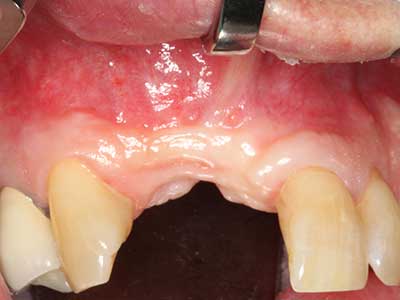

Fig. 16: También condiciones intraorales estables con incorporación de los implantes en la encía queratinizada.

Fig. 17: Tomografía computarizada de un osteoma de crecimiento progresivo ...